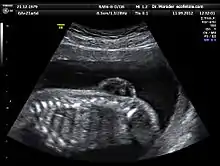

L’échographie est la principale et la plus courante des méthodes de diagnostic prénatal. En France, il est ainsi obligatoire de pratiquer trois examens échographiques[7], à 12, 21, puis 33 semaines d’aménorrhée.

Cette technique permet, grâce à l’utilisation d’ultrasons, de voir le bébé par image de synthèse. Elle permet de contrôler l’avancée de la grossesse et détecte un certain nombre de malformations ou de signes avant-coureurs de maladies génétiques. Par exemple, cet examen est l’un des trois composants du « triple test » en vue du dépistage de la trisomie 21, car il permet la mesure de l’épaisseur de la nuque, signe d’appel de cette affection[8].

Le premier examen échographique permet d'exclure des malformations de l'utérus et des tumeurs génitales, de déterminer le nombre de fœtus, de constater la vitalité du/des fœtus, de vérifier l'âge gestationnel en mesurant la longueur vertex-coccyx, de mesurer l'œdème nucal du fœtus et de vérifier la morphologie (tête, thorax, extrémités).

Le 2e examen a pour but principal l'observation de l'anatomie fœtale, afin de montrer directement des malformations fœtales ou de les suspecter à l'aide d'indices indirects. La quantité de liquide amniotique est aussi évaluée, ainsi que la position et la morphologie du placenta[9].

Le 3e examen doit permettre d’évaluer le développement fœtal, le fonctionnement régulier du placenta ainsi que le positionnement exact du fœtus et les problèmes éventuels de cordon ombilical en vue de l’accouchement[10].